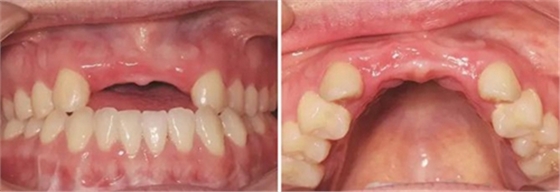

圖1 植骨術(shù)前口內(nèi)正面觀 圖2 植骨術(shù)前口內(nèi)頜面觀

患者,女性,23歲,大學(xué)生?;颊哂?年前因外傷導(dǎo)致上前牙缺失,期間行可摘局部義齒修復(fù),自覺每天摘帶不便,且影響正常發(fā)音及美觀,至我科要求種植修復(fù)。平素體健,無(wú)全身系統(tǒng)性疾病,無(wú)特殊藥物服用史,無(wú)藥物、材料等過敏史,無(wú)吸煙、夜磨牙等不良習(xí)慣。口外檢查見口腔頜面部對(duì)稱,張口度正常,中位唇線,中位笑線??趦?nèi)檢查見12、11、21、22缺失,缺牙區(qū)牙槽嵴薄。覆牙合覆蓋淺,23反牙合??谇恍l(wèi)生狀況良好。拍攝CBCT示:12位點(diǎn)可用牙槽骨高度為16.4mm,寬度為3.6mm;22位點(diǎn)可用牙槽骨高度為19.5mm,寬度為3.2mm。